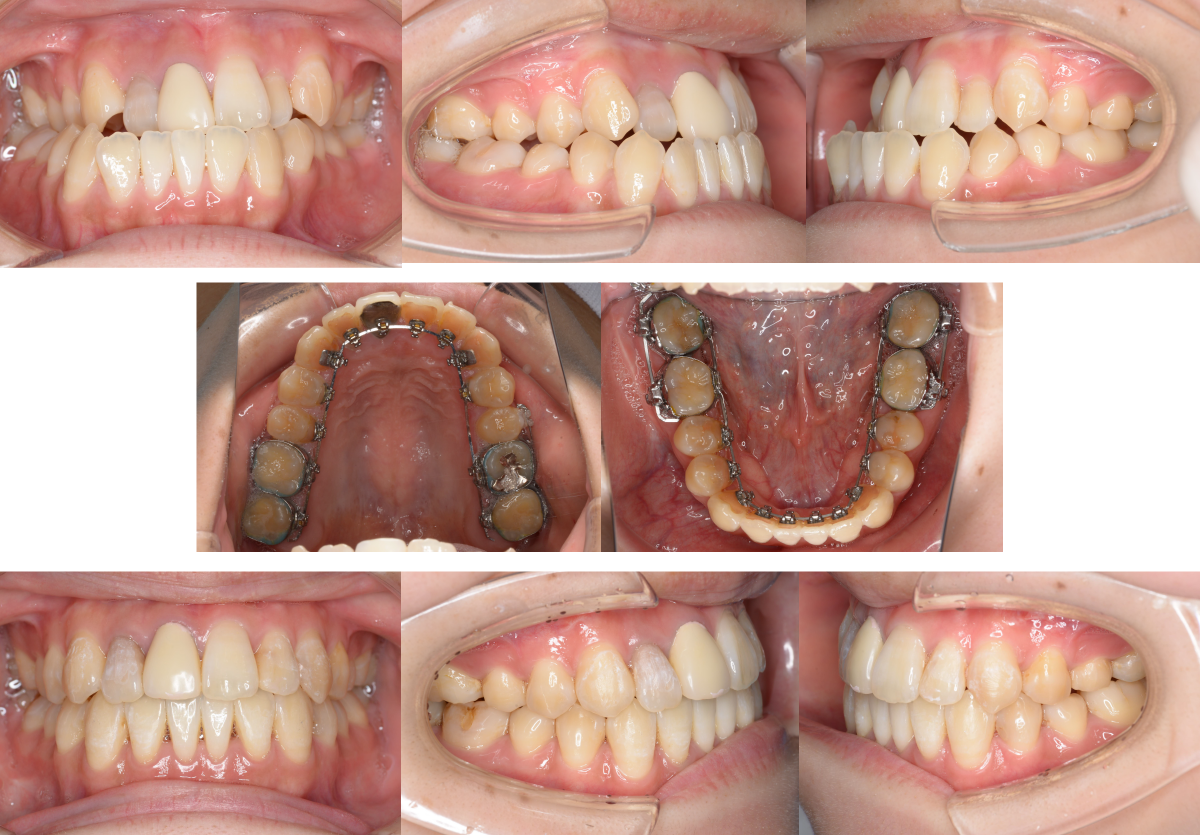

①顎矯正手術(外科矯正)の矯正治療例(20代女性・治療期間2年)

| 年齢・性別 | 20代女性 |

| 治療期間 | 2年 |

| 抜歯 | なし |

| 治療費 | 100万円(調整費、保定費まで含む総額制) |

| 備考 | 裏側矯正 |

| リスク・副作用 | 痛み・治療後の後戻り・歯根吸収・歯髄壊死・歯肉退縮 |

川崎市からご来院の20代女性で、受け口(反対咬合)と交叉咬合(すれ違い)の症状がありました。

治療法は裏側矯正(舌側矯正)で、治療期間は2年です。

非抜歯で矯正治療を行い、キレイな歯並びになりました。